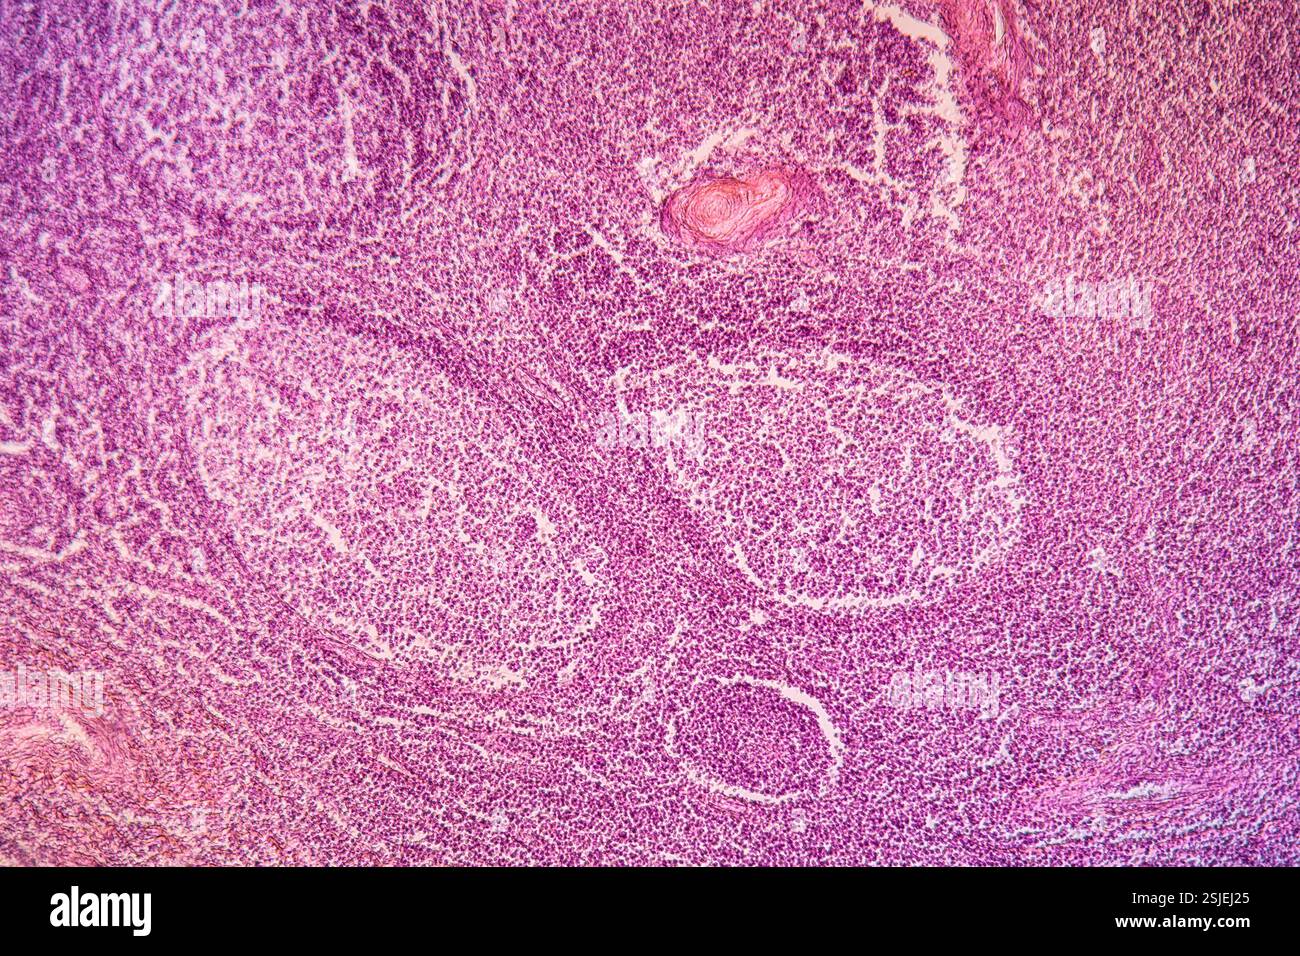

Tonsillen erkranktes Gewebe 100x Stockfotohttps://www.alamy.de/image-license-details/?v=1https://www.alamy.de/tonsillen-erkranktes-gewebe-100x-image648168925.html

Tonsillen erkranktes Gewebe 100x Stockfotohttps://www.alamy.de/image-license-details/?v=1https://www.alamy.de/tonsillen-erkranktes-gewebe-100x-image648168925.htmlRF2SJEJ25–Tonsillen erkranktes Gewebe 100x